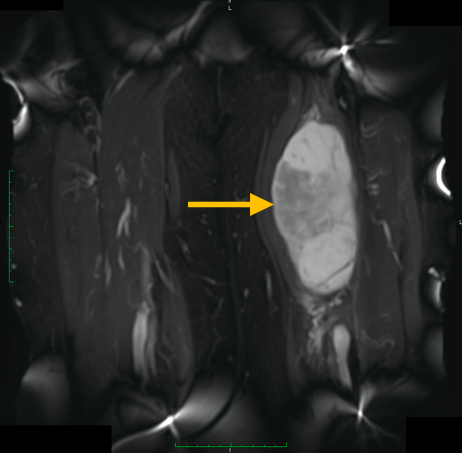

Radiographic imaging is used to help form a diagnosis. These include X-Ray, MRI, CT and Bone Scans.

An example of an MRI is shown.